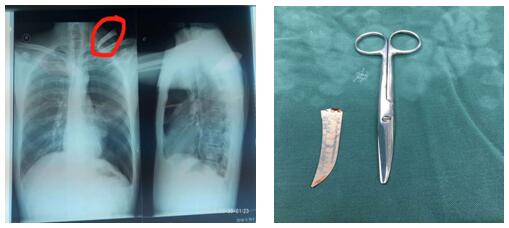

患者左颈根部可见一长约2cm伤口,边缘整齐,内插入刀片断端出血不止。左颈根部刀刺伤常常会损伤颈胸部大血管导致大出血危及生命、同时会造成开放性气胸危及生命,病情非常危急,需行急诊开胸探查术。苗主任与李伟主治医师、李仁栓主治医师立即制定了手术方案。1:40分患者被送进手术室,在全麻下行胸腔镜探查楔形切除、肋间血管缝合,胸壁伤口清创术。手术紧张有序地进行。凌晨4点钟患者安全返回病房,手术顺利完成。从患者颈部取出的刀片长约10cm 左右。